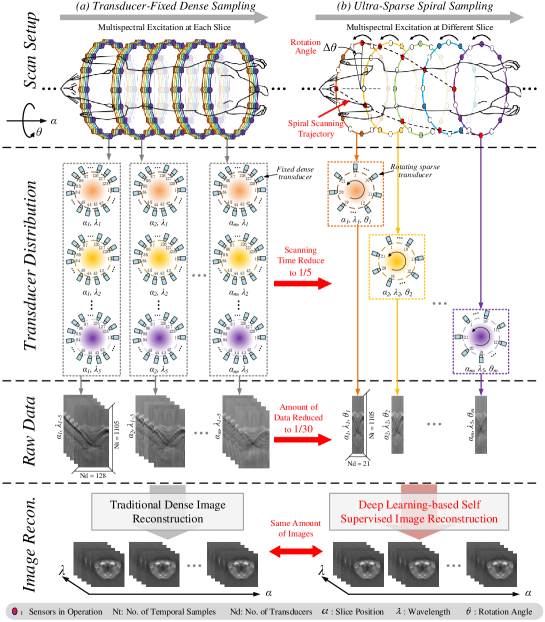

Conventional PAT imaging system usually employs a linear or ring-shaped transducer for data acquisition, and the acquired images are 2D cross-sectional images. With linear translation scanning, a 3D volume image can be obtained, as shown in Fig.1 (a). To further perform multispectral imaging, one image is obtained per excitation wavelength. The total data amount and acquisition time increase with the number of wavelengths and slices. Therefore, multispectral and 3D PAT imaging has a heavy time cost and is very inefficient.

For cross-sectional PAT with a ring-shaped transducer, the axial displacement between two slices is on the order of sub-millimeters. Therefore, there is a wealth of information shared between slices that may enable sparser sampling. Inspired by this, we propose to combine the technique of spiral scanning with multispectral interlaced sparse sampling to further reduce the sparse sampling rate. As shown in Fig.1 (b), our approach, which is dubbed ultra-sparse spiral sampling PAT or U3S-PAT, involves the simultaneous rotation and translation of the sparse ring-shaped transducer each time the excitation wavelength is changed. By doing so, our U3S-PAT facilitates multi-wavelength and multi-slice cross-sectional imaging that covers the entire region of interest with much fewer measurements. To solve the highly ill-conditioned image reconstruction problem, we develop a novel self-supervised image reconstruction model that does not require any ground truth for network training and only relies on intrinsic information of the raw PA signal. Provided by our unique U3S-PAT scanning strategy, we incorporate a structural prior image that fuses the redundancy information among slices and wavelengths to guide image reconstruction. To assess the performance of the proposed U3S-PAT strategy, we simulate the acquisition of spiral scanning data on a commercial PAT system and conduct in vivo animal experiments. The results demonstrate that even with a sparse sampling rate as low as 1/30, the reconstruction image quality and spectral unmixing accuracy achieved using our U3S-PAT are similar to those obtained with full-angle, all-wavelength dense sampling.

Our U3S-PAT method is based on a cross-sectional multispectral PAT system with a ring-shaped array transducer. Currently, most of popular PAT systems are based on the dense sampling strategy [Fig.1 (a)], where the transducer array consists of a large number of elements (e.g., the total number of elements ) to ensure dense angular coverage. Either the transducer or the imaging target is linearly translated for imaging of different slices. At each slice position, multiple sets of signal are obtained for multispectral imaging. Therefore, the dense sampling scheme inevitably generates a large amount of data, i.e., the total size of acquired data is , where is the number of temporal samples obtained by each detector, is the number of excitation wavelengths in each slice and is the number of scanned slices.

In our U3S-PAT strategy [Fig.1 (b)], a sparse transducer array is used (e.g. ). During scanning, each time the excitation wavelength is switched from one another, in the meantime, the transducer rotates for a small angle around the imaged object and translates a specified distance along the axial direction. Therefore, the slice position, scanning wavelength, and angle of the transducer are changed per image simultaneously. A spiral scanning trajectory is formed for the transducer. To make full use of the angular spacing between two adjacent transducer elements, the transducer is rotated such that each measurement is evenly distributed. That means, letting be the angle between two adjacent elements, the angle rotated by the transducer as the laser transits from one wavelength to another is . Therefore, the rotation angle at the tomographic position is denoted as , where .

As a comparison, under our U3S-PAT strategy, the total size of the acquired data is only , where is the downsampling rate of transducer elements. Therefore, compared to dense sampling, the total sparse sampling rate is . For example, for , compared to dense sampling using 128 elements, we can reduce the amount of data to 1/30 with 21 elements, i.e. . More importantly, our U3S-PAT strategy reduces multispectral scanning time during 3D imaging. To image the same number of slices, the time it takes for traditional transducer-fixed PAT to perform wavelength imaging can be reduced to only . Since only one wavelength is used at each slice, the imaging speed of U3S-PAT is limited by the wavelength switching time. Therefore, our U3S-PAT may enable 3D multispectral imaging of dynamic scenes such as the beating heart, thus making possible the visualization of oxyhemoglobin () and deoxyhemoglobin () within the heart during cardiac cycles.